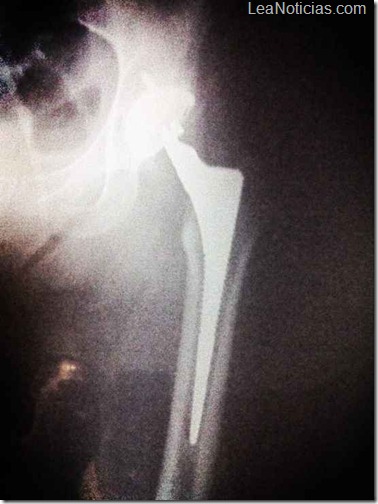

Alejandra Guzmán, compartió a través de su Twitter, una fotografía de la radiografía que se le tomó del fémur para mostrar a sus seguidores cómo estaba antes de la operación.

Dicha imagen estaba acompañada de: «La podemos reconstruir, Sera La Guzman Bionica», escribió ?@Al3jandraGuzman. La operación ha sido un éxito, y la Guzmán deberá permanecer un mes inmovilizada.

La cirugía, una artroplastia de cadera izquierda, duró aproximadamente tres horas.